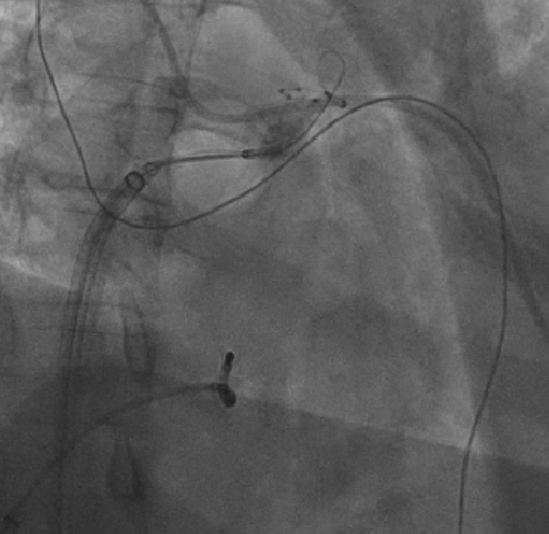

冷冻消融球囊紧贴右心耳消融中(X线影像)